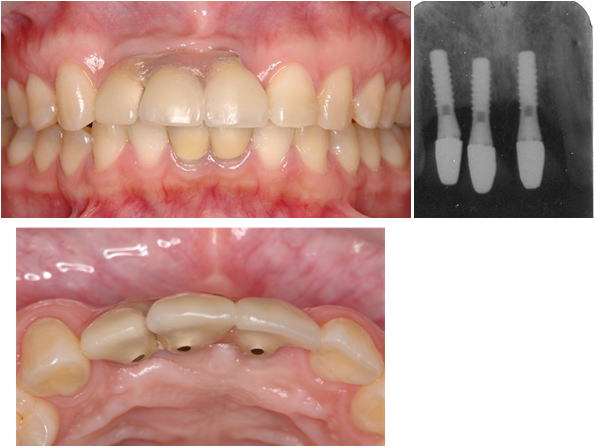

歯がなくなり、骨がやせてしまった場合は、骨を増やす処置をしてインプラント治療をしなければ下図のような審美的に良くない結果になります(他院で治療を受け、再治療を行うことになった患者さん)。

4.極度の骨・軟組織欠損がある2歯欠損症例

(他院でトラブルとなった症例 2の再インプラント治療、自家骨移植と有茎口蓋弁移植)

まず予後不良インプラント撤去し、極度の骨欠損があったが、オトガイ部から10mmの厚みの皮質海綿ブロック骨移植にて審美的インプラント治療を行いました。歯肉の厚みを増やすために有茎口蓋弁移植も併用しました。